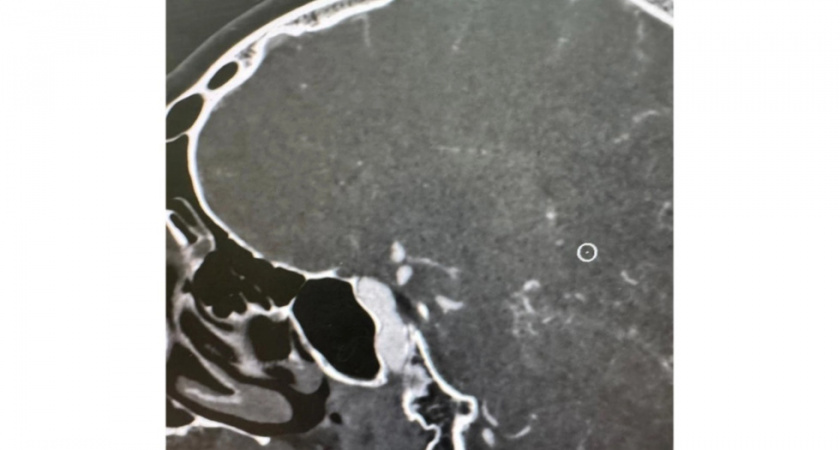

Житель Саратовской области, внезапно потерявший сознание и впавший в кому из-за разрыва аневризмы сосуда головного мозга с последующим кровоизлиянием и отеком мозга, успешно прооперирован в Рязанской областной клинической больнице. Медицинское учреждение сообщило об этом в своих социальных сетях.

По словам медиков, молодой человек, находившийся в полном расцвете сил, резко почувствовал слабость, после чего потерял сознание и не приходил в себя. Диагноз был крайне серьезным: разрыв аневризмы сосуда головного мозга с обширным кровоизлиянием и отеком.

После экстренного обследования пациента доставили в реанимационное отделение, где реаниматологи стабилизировали его состояние. Далее последовала сложнейшая операция, потребовавшая участия двух хирургических бригад.

В Рязанской ОКБ подчеркнули уникальность случая, обусловленную необходимостью проведения двух последовательных операций для спасения жизни пациента. В настоящее время пациент находится в отделении реанимации, его состояние стабильное, он находится в сознании.